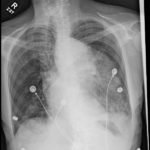

The patient’schest X-ray revealed a prominent mediastinum and opacification in the left middle and lower lung fields. The CT showed an aortic aneurysm extending from the thorax to the abdomen with rupture near T7 (blue arrow). It also showed periaortic hemorrhage with active extravasation (green arrow) likely secondary to a penetrating ulcer and bilateral pulmonary opacities concerning for hemothorax (pink arrow).

Thoracic aortic aneurysm (TAA) is a progressive and potentially deadly disease with a poor prognosis when left untreated.1 Most TAAs are asymptomatic and may be detected incidentally on imaging. Although presentation can vary, chest or back pain might be the first presenting symptom and can represent rapid expansion, acute dissection, or rupture.2 In the acute setting, chest X-ray might be the first imaging study performed during the initial evaluation of a patient with symptoms that suggest a potential for aortic disease. Predictive sensitivity of a widened mediastinum or abnormal aortic contour can be around 64% and 71% respectively, but the sensitivity of CXR is not adequate to definitively rule out acute aortic disease.3 CT with contrast remains the imaging study of choice for diagnosis of acute thoracic aortic disease; it can be nearly 100% sensitive and can also demonstrate the presence of a dissection flap or rupture.3